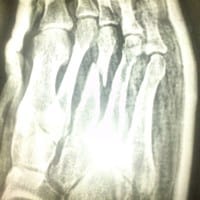

Me partí el tercer metatarsiano hace un año, y me sigue doliendo, necesita operación?

Me partí el 3 metatarsiano Del pie derecho en un accidente hace casi un año, no me hicieron nada y el pie aún me duele y se me hincha continuamente. ¿Necesito operación? ¿O alguna terapia para solucionarlo? ¿O algún medicamento para sanar?

Fractura 3 metatarsiano pie derecho

respondió: Creo que la fractura debieron intentar reducírtela en urgencias, y no sólo inmovilizar sin hacer que los fragmentos "coincidan". La consecuencia: opino como los compañeros fisioterapeutas: la fractura está muy desplazada y es poco probable que vaya a...